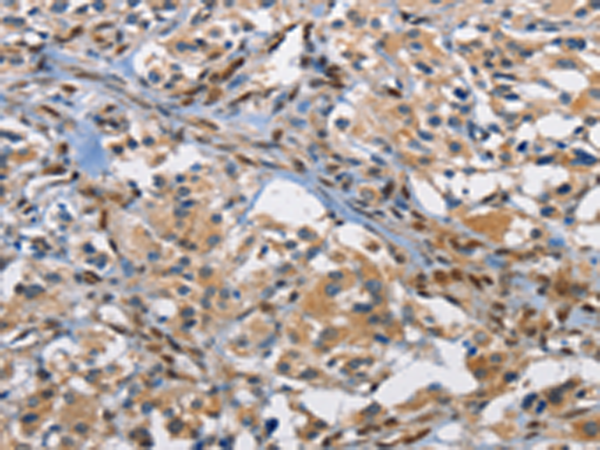

分类: 科研抗体货号: P00237别名: CPSB, ACC-4, ACC-5, minichain应用: WB,IHC反应种属: Human, Mouse, Rat